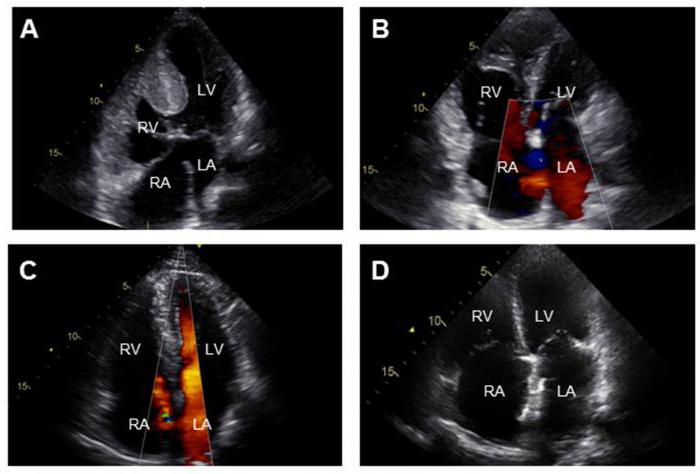

- Электрокардиография. Помогает определить активность и работу сердца, изменения в нем.

- Эхокардиография. Помогает оценить степень поражения органа и характер нарушения в работе.